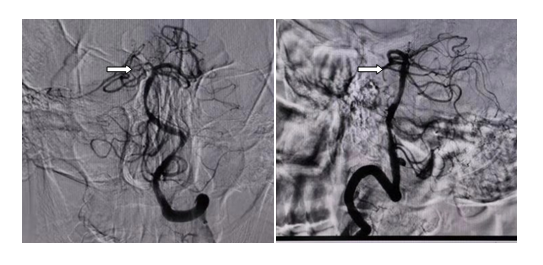

取栓非常成功,取栓后,患者神志清楚,四肢活动自如。

白箭头所指为闭塞的基底动脉取栓开通后